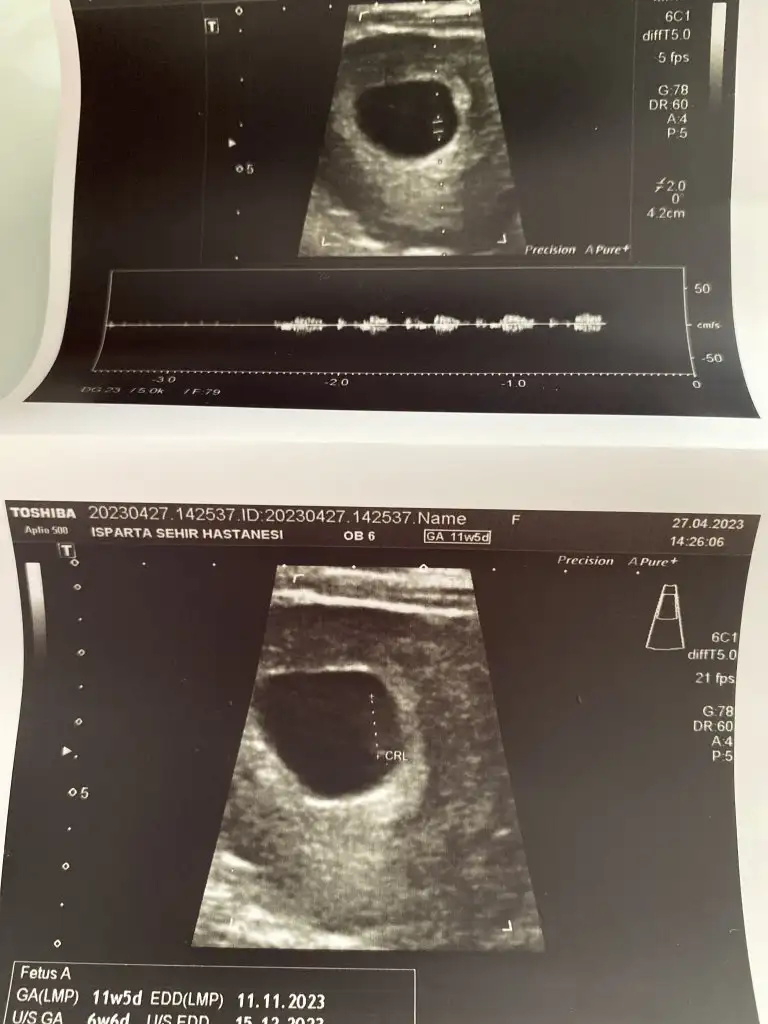

Herkese günaydın. Ben dün ikili test sonucumu almaya gittim, gitmişken de muayene olayım dedim bebek duruyor mu diye

doktor o sırada bir şeyle meşguldu, asistanı baktı, sekreteri de bilgisayardan asistana okudu riskleri. Yaş riski hariç düşük çıktı (yaş 1/59, down 1/1035 trisomi 18 13 1/300000 civarı). Güzel dediler (yaştan dolayı zaten fetal yaptıracağımı biliyorlardı) sonra sonucu istedim ama devlet hastanesi olduğu için yazıcıya gönderiyorlar, çıkarken alıyorsunuz bankodan. Alınca kan değerlerimin birinin yüksek olduğunu fark ettim. Serbest beta hcg 2.33 mom (papp-a mom 1.84) çıkmış ve doktorla konuşma şansım olmadı hiç (muayene sırasında riskler konuşuldu sadece kan değerlerini okumadı sekreter, gündeme gelmedi yani), bugün fetal için kan vereceğim ama geceden beri sözelci-dilci halimle tıp makalelerini tarıyorum (kimi 1.5 mom üstü kimi 2.5mom üstü yüksek kabul ediyor ve down olasılığına ek olarak preeklamsi, hipertansiyon vb gibi birçok gebelik komplikasyonuna işaret edebileceği söyleniyor, çoğu bulgu papp düşük bu yüksekse sorun diyor ama atipik bulgular da büyük bir oranı oluşturuyor vb.) şu aşamada burada böyle bir deneyimi olan yoktur muhtemelen ama yine de belki bir fikri olan vardır diye yazmak istedim. Bir de kombine risk, biyokimyasal risk vb hesaplanmamış hiç. Acaba riskleri hesaplarken kan değerlerini dahil etmediler mi demek oluyordur bu? Fetal için kan vereceğim bugün ama sonucu bekleyebilir miyim bilemedim.